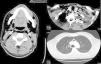

Secciones transversales de TC a nivel mandibular, cervical inferior y mediastino superior. Se observa un extenso enfisema que diseca los planos musculares cervicales bilaterales y afecta los espacios parafaríngeo y prevertebral, el suelo de la boca, el espacio submandibular y el espacio cervical posterior, llegando al mediastino y causando un neumomediastino. Estos hallazgos son asimétricos y más evidentes en el lado derecho.

Paciente de 30 años que acudió a urgencias por crepitación a nivel de cara, cuello y tórax tras extracción del tercer molar derecho mandibular el día anterior. El paciente no refería disnea, ni dolor, ni tumefacción. A la exploración: hemodinámicamente estable, saturación de oxígeno al 100% y un evidente enfisema subcutáneo en el lado derecho de la cara, región laterocervical y lado derecho del tórax superior. Se realizaron: analítica, que fue normal; radiografías cervical y torácica, que mostraron un importante enfisema subcutáneo y neumomediastino; y una tomografía computarizada (TC) (fig. 1). El paciente fue ingresado para antibioterapia profiláctica y observación. Evolucionó favorablemente, con disminución progresiva del enfisema, sin aparecer ninguna complicación, por lo que fue alta al cuarto día.